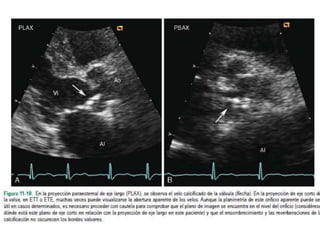

Área valvular por planimetría 2D

Paraesternal eje corto en la punta de las valvas

Puntos clave:

• Identificar el orificio de la válvula estenótica, en forma de túnel.

• El modo de zoom se utiliza para enfocar el orificio valvular, con la ganancia reducida para

mostrar claramente la interfaz tejido-sangre.

• Para obtener el área valvular, se traza el borde interior de la interfaz negro-blanco.

• Normalmente, en los pacientes sin intervenciones previas el orificio tiene una forma lisa y

elíptica.

• Tras valvuloplastía percutánea o quirúrgica, el orificio es más irregular debido a la separación

de las comisuras fusionadas.

Paso 2: Evaluarla gravedad de la EM Cont… Área valvular por planimetría 2D Paraesternal eje corto en la punta de las valvas Puntos clave: • Identificar el orificio de la válvula estenótica, en forma de túnel. • El modo de zoom se utiliza para enfocar el orificio valvular, con la ganancia reducida para mostrar claramente la interfaz tejido-sangre. • Para obtener el área valvular, se traza el borde interior de la interfaz negro-blanco. • Normalmente, en los pacientes sin intervenciones previas el orificio tiene una forma lisa y elíptica. • Tras valvuloplastía percutánea o quirúrgica, el orificio es más irregular debido a la separación de las comisuras fusionadas.